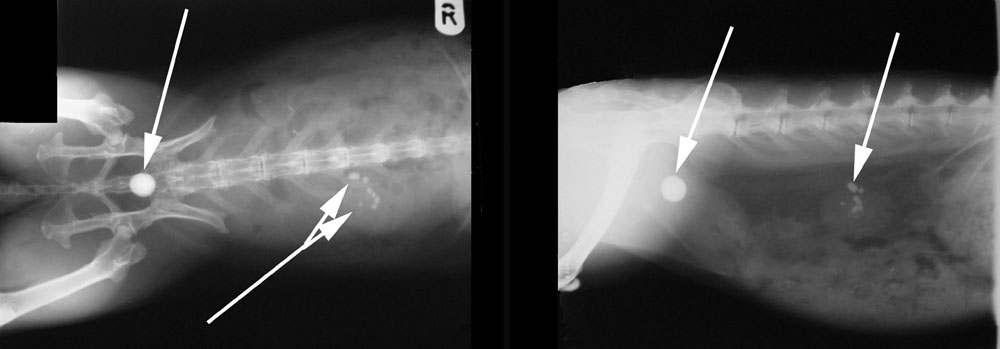

De diagnose van blaasgruis wordt gesteld op basis van de klachten die we met u bespreken, in combinatie met een lichamelijk onderzoek en verder onderzoek zoals urine-onderzoek en röntgenfoto’s of echo. Wanneer we in de buik voelen kan het zijn dat de blaas erg dik en stevig aanvoelt (als een zakje met zand) of kun je soms steentjes voelen. De blaas is vaak erg gevoelig. Soms kan er roodheid en ontsteking van de huid rond de penis of vulva worden gezien door irritatie van de zanderige urine. Dit soort bevindingen geven vaak al het vermoeden van een blaasprobleem. Door urine te bekijken kunnen we een idee krijgen van de hoeveelheid gruis of zand en kunnen we zien of er bloed en ontstekingscellen in de urine aanwezig zijn. Vooral ook wanneer de urine rood verkleurd is, is het fijn te weten of dit daadwerkelijk bloed is of gewoon kleurstoffen.

Met röntgenfoto’s of echo kunnen we niet alleen een idee krijgen van de hoeveelheid gruis in de blaas, maar kunnen we ook zien of er mogelijk elders steentjes te zien zijn in de urinewegen, bijvoorbeeld in de nieren of de plasbuis. Ook kun je met beeldvorming andere problemen uitsluiten, zoals problemen ter hoogte van de baarmoeder of bijvoorbeeld een blaastumor.